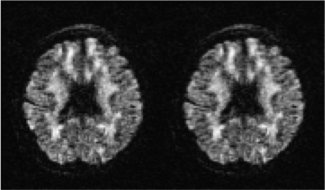

平均多次扫描:若是对于一位被试进行了多次扫描,需对多次扫描图像进行平均,如图5.27所示。

图5.27 平均多次扫描示意图